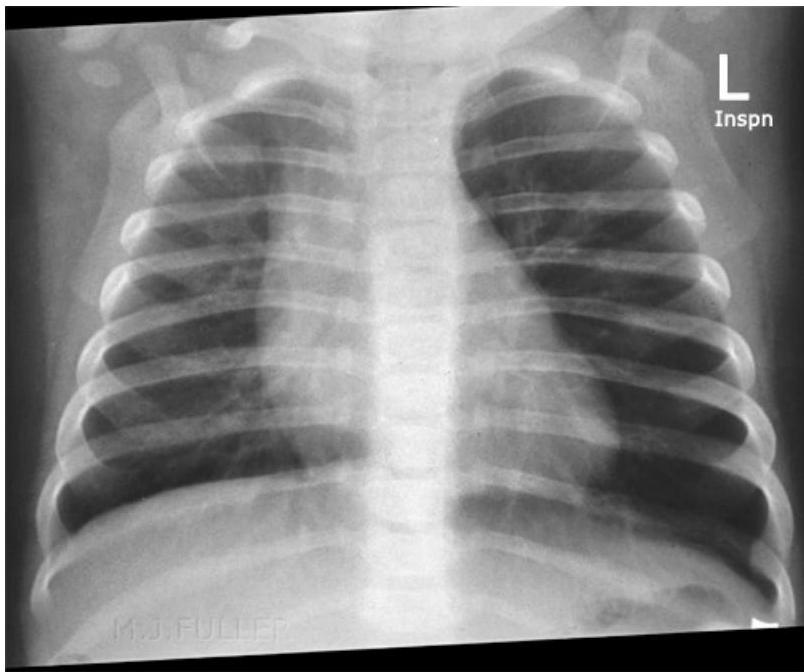

- Expiratory Chest X-ray or Fluoroscopy:

- Indicated for children with a suggestive presentation but normal inspiratory X-ray.

Radiological Findings:

- On Inspiration: Lungs may appear similar as airways widen, allowing air past the FB.

- On Expiration: The FB can obstruct the bronchus as its diameter decreases. The greatest difference in lung aeration is seen here, as air is trapped in the affected lung while exhaled from the normal lung.